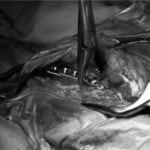

脊髄の減圧、脊柱管の再構築・安定化を目的に、片側椎弓切除術およびMatrixMANDIBLE Plateによる椎体固定を実施しました。

隣接椎体を架橋するようにプレートを設置しました。

術後レントゲン写真